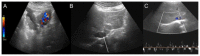

Uterine intravenous leiomyomatosis is an uncommon tumor, usually arising from the uterus, with nodular masses which extend intravascularly over variable distances and may reach the inferior vena cava, right atrium, and pulmonary arteries. Early diagnosis and surgical intervention are crucial as intracardiac leiomyomatosis not only causes cardiac symptoms but may result in pulmonary embolism and sudden death. Complete tumor resection is key in disease management, thus rendering cardiac-extending uterine intravenous leiomyomatosis one of the most challenging conditions for surgical treatment. The use of interventional radiology procedures can facilitate the surgical approach. We report the case of a massive pelvic recurrence of uterine leiomyomatosis with intracardiac extension and pulmonary embolism, analyzing management and surgical outcomes, highlighting the role of interventional radiology during the therapeutic pathway. Nonetheless, there are currently very few data available concerning the use of interventional radiology procedures in the therapeutic strategy of uterine intravenous leiomyomatosis with intracardiac extension.